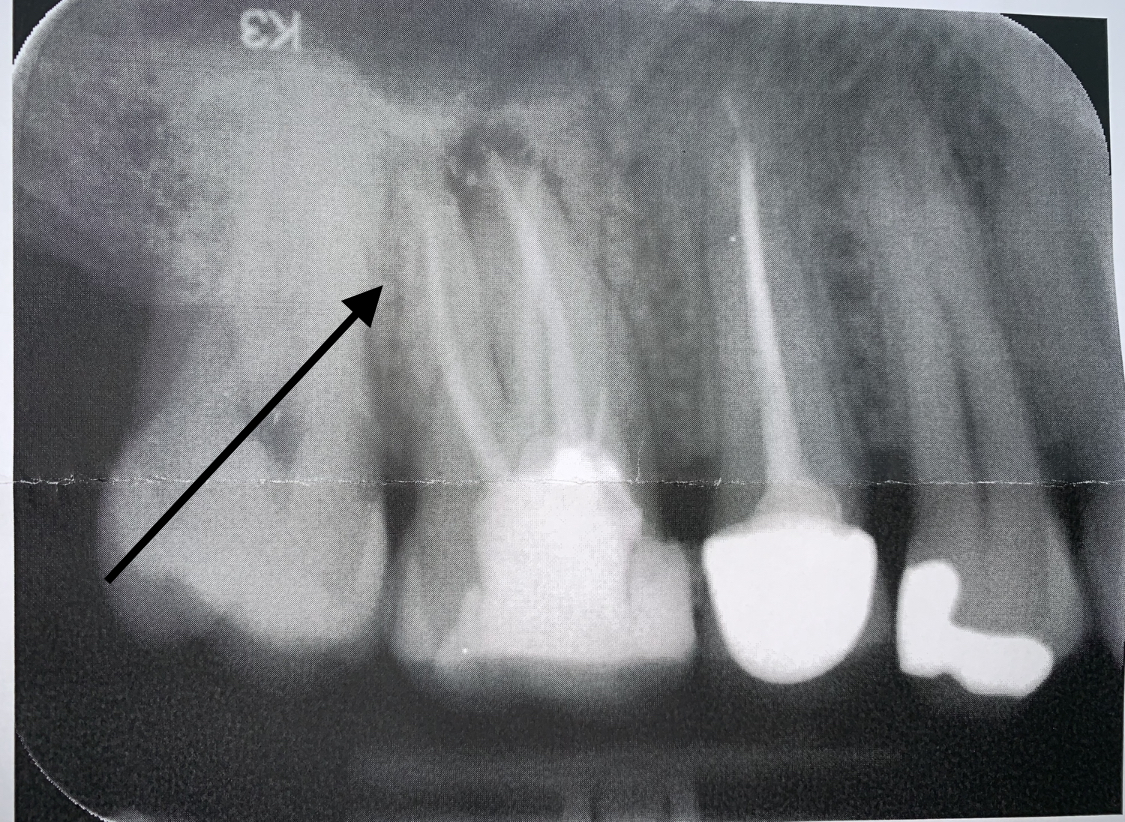

Voor een second opinion ben ik langs een andere tandarts geweest en die zag dat er degelijk een wortelpuntonsteking zit.

Wat moet nu het beste doen? Wederom en wkb of langs de kaakchirug voor een Apex?